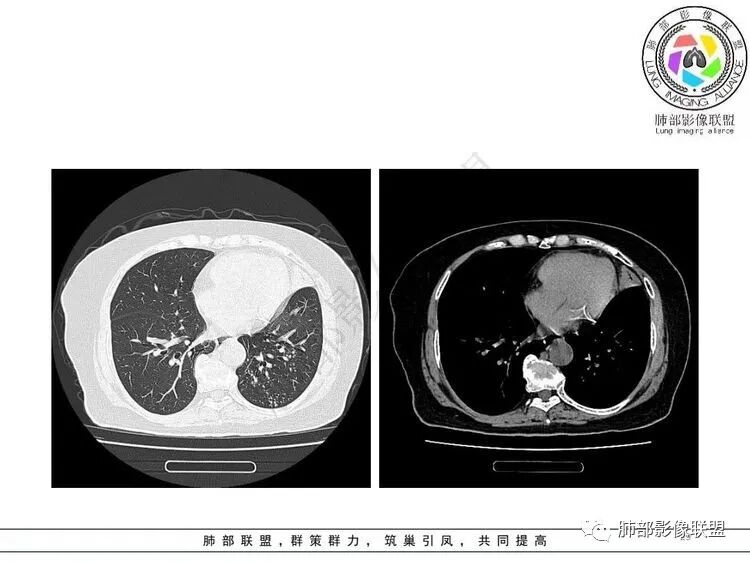

左肺上叶大片状实变,边缘部分清晰,密度不均,支气管部分扩张扭曲,同时散在分布小透光区,左下肺沿肺段及纹理走形斑点,粟粒影及树芽征。考虑左肺感染性病变,结核首选,其它感染待排

女,65胸闷,气促半月入院,左肺上叶见大片状实变影,边缘模糊,其内见含气支气管征,支气管管壁不规整,凹凸不平,广泛性狭窄、僵硬、扭曲,左肺下叶另见粟粒,结节及树芽征征,结核感染T细胞阳性,考虑结核可能,除外其它感染性病变。

老年女性,糖尿病,不发热,影像左肺上叶大片状实变,边缘部分清晰,密度不均,支气管部分扩张扭曲,左肺下叶可见粟粒影及树芽征。考虑左肺感染性病变,首先结可能性大核,NTM待排除。

老年女性,有糖尿病病史。边缘模糊不清,左肺上叶大片状实变密度影,内可见支气管穿行,走形迂曲并扩张,另左肺下叶多发点状高密度影,并树芽征,考虑结核

3.左肺上叶较大范围实性密度区,密度偏高不均,支气管穿行且轻度扩张,可见无壁不规则空洞(未能显示外壁),未显示液平或腔内结节。

4.左肺下叶多发结节影及条索影,密度不均,边界较清楚,可见树芽征。

1.左肺上叶较大范围实性密度区,支气管未见阻塞,无壁空洞,整体比较“干”,加之纵隔左移,比较符合病程较长的结核性病变。

左肺下叶多发结节影、条索影、树芽征等具有相当明显的提示意义—符合继发性肺结核。